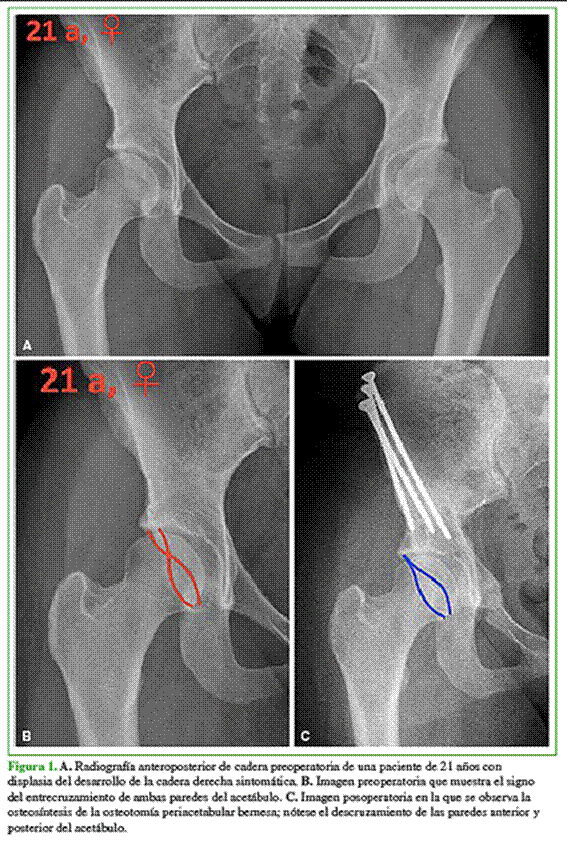

La evaluación radiográfica preoperatoria incluyó una incidencia de pelvis anteroposterior que permitió clasificar a los pacientes y determinar los ángulos acetabulares, y una de perfil del lado afectado con medición del ángulo alfa. Todos los casos correspondían al grado I de la clasificación de Crowe,12 porque tenían un desplazamiento proximal <10% y una subluxación de la cabeza femoral <50%. La mediana del índice acetabular (IA) preoperatorio era de 19° (RIC 16-20) para el grupo A y 17° (RIC 15-18) para el grupo B (p = 0,14). La mediana del ángulo centro-borde lateral (ACBL) preoperatorio era de 16° (RIC 8-19) para el grupo A y 19° (RIC 10-20) para el otro grupo (p = 0,19). Solo en siete y seis pacientes del grupo A y B, respectivamente, se observó una retroversión acetabular verdadera, definida por la presencia de dos de los siguientes signos radiográficos: signo del entrecruzamiento, signo de la pared posterior y signo de la espina ciática (p = 0,74) (Figura 1). En ambos grupos, se evaluó el compromiso articular utilizando la clasificación de Tönnis.13 El deterioro articular fue similar en ambos grupos y, en ningún caso, fue superior al grado 2 (p = 0,91) (Tabla 1).